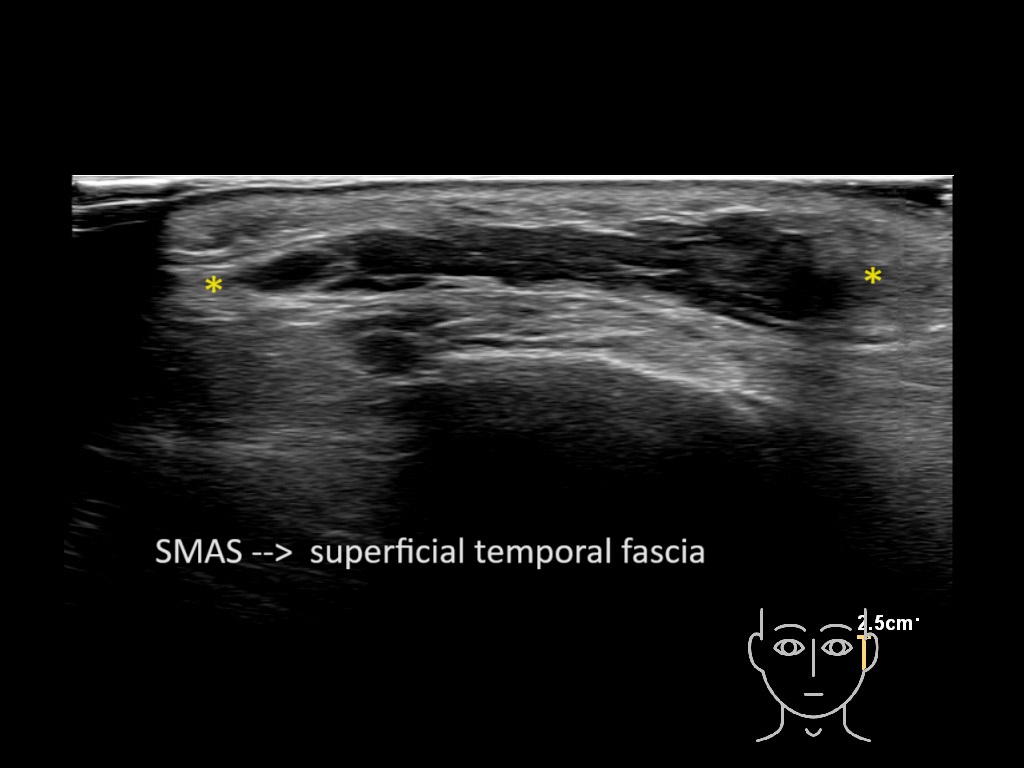

Filler behavior - Temple zygoma US

Study the first image to recognize the different layers. If you are sure about the layers, swipe to the second image to view the answer (if applicable).

Hover over an image to view the secondary image or click on the image title for more information.